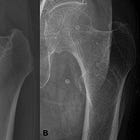

Beyond symptom relief, MHT/ERT has the well-documented ability to slow bone loss through osteoclast-mediated bone resorption. By preserving bone mineral density, estrogen MHT can reduce hip fracture risk by 1/3rd.

Summarized above in Figure 3 from the JAMA publication, MHT appeared to increase the risk of breast cancer, dementia, and cardiovascular disease. However, the trial did confirm the benefit of MHT in reducing fracture risk. The balance of risk led the FDA to apply a blanket black-box label to all estrogen containing MHT products.

For the millions of women in their 40s and 50s experiencing debilitating vasomotor symptoms, the practical effects of relabeling could be transformative. The gap between the 40 million women who might benefit and the 2 million who currently receive therapy is not explained by clinical contraindications alone. Importantly, this gap - two decades of women who went through menopause with MHT support - won’t benefit from this relabeling change. These women, now in their 50s, 60s, and 70s have already preserved through menopause and experienced irreversible changes to their physical health, including the silent bone loss that will likely go undetected until fracture. Much of this impact appears explained by fear rooted in a warning that, for the intended population of younger menopausal women, that may be overstated given the magnitude of risk observed in the WHI.